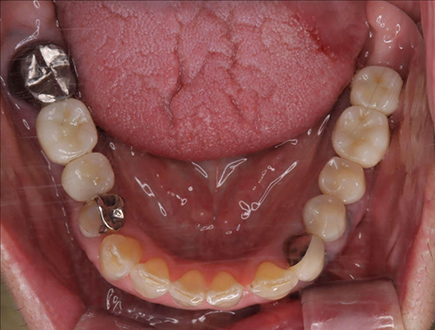

インプラントの症例

口腔外科専攻医が担当します

インプラントは専門性の高い外科的な処置です。

当院では、大学病院での経験を持つ口腔外科専攻医がすべての治療

を担当し、安全性に配慮した治療を行っています。

| 治療部位 | 左側下顎臼歯部 |

|---|---|

| インプラント本数 | 2本 |

| 単価 | 40万円/本 |

| 合計費用 | 80万円 |